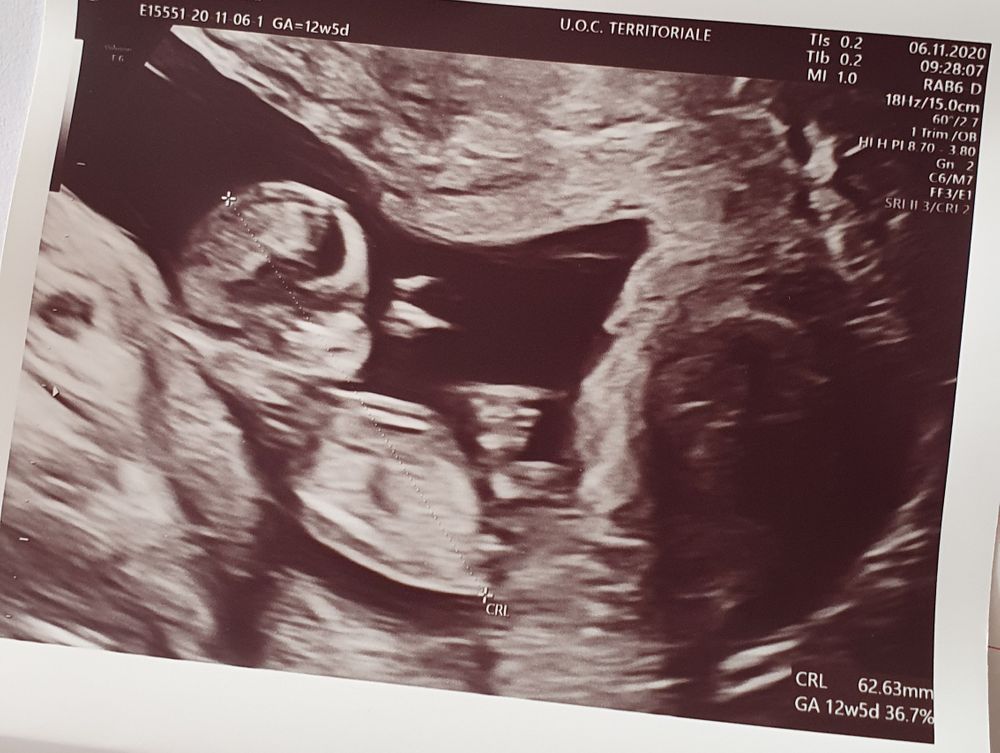

Узи первого триместра форум

Узи первого триместра форум 117 фото